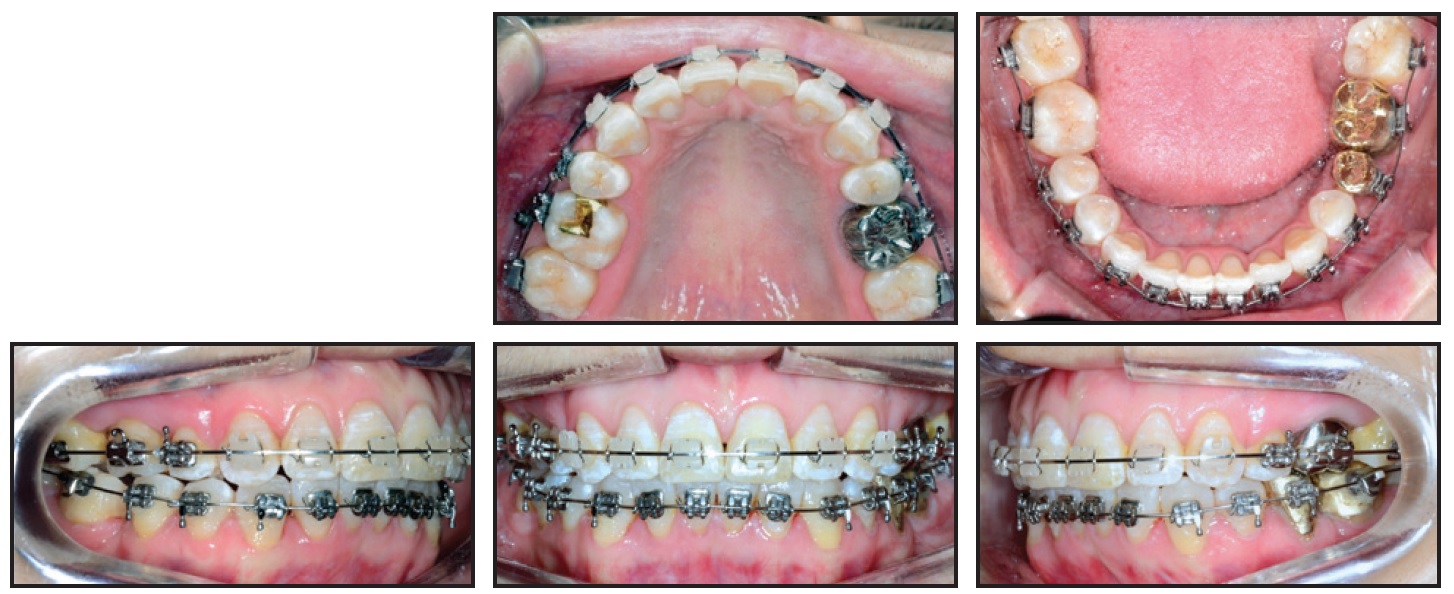

Standard-prescription .022" Damon MX* self-ligating brackets were bonded in both arches, except for the lingually displaced lower right central incisor. One month later, an open-coil spring was inserted mesial to the lower right canine on the initial .014" Copper NiTi archwire to open space for the displaced incisor (Fig. 2).

Fig. 2 Initial .014" Copper NiTi** archwire with U-shaped segmental wire in lower anterior segment.

A segmental U-shaped arch was added and slightly activated distally to control the lower incisors while avoiding any protrusion. The .014" Copper NiTi archwire was maintained for seven months, until the wire was completely passive in the slots, and was then replaced by an .014" × .025" Copper NiTi archwire. Minor interproximal stripping of the lower incisors was performed to facilitate leveling and alignment.

The lingually displaced lower right incisor was bonded after 23 months of treatment, when sufficient space had been opened for its traction and alignment. Torque control was then needed to align the roots of the lateral incisor buccally and the central incisor lingually. Because it is difficult to control torque on a round archwire, an inverted, U-shaped .017" × .017" TMA* segmental wire was inserted into the vertical bracket slots (Fig. 3). The .014" × .025" Copper NiTi archwire was inserted passively to control torque in all teeth until uprighting and alignment were complete.

Fig. 3 After 23 months of treatment, showing torque control of lower right central and lateral incisors with inverted, U-shaped .017" × .017" TMA** wire in vertical slots.

The .014" × .025" Copper NiTi archwire was inserted passively to control torque in all teeth until uprighting and alignment were complete.

In the Damon System, the patient’s archform is recorded with a wax bite registration at this stage, allowing for complete expression of the perioral musculature and the alveolar bone remodeling that occurs after arch expansion.9 The system then provides further expansion in the canine, premolar, and molar regions. In this case, the diagrammed .017" × .025" TMA archwires were inserted after 28 months of treatment for additional torque control and arch preparation. Finishing .019" × .025" TMA archwires were used for the last month (Fig. 4).

Fig. 4 After 34 months of treatment, showing .019" × .025" TMA finishing archwires.